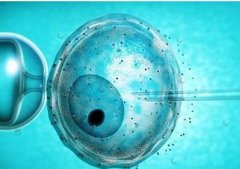

卵泡监测是如何进行的

卵泡监测是如何进行的监测卵泡的时间,医生会根据病人的身体情况而定。监测期间,医生通过B超,可以发……

试管婴儿胚胎移植后前为什么会

试管婴儿胚胎移植后前为什么会1、在移植术后的早期阴道少许咖啡色血性分泌物可能是移植过程中碰触宫颈糜烂面导……